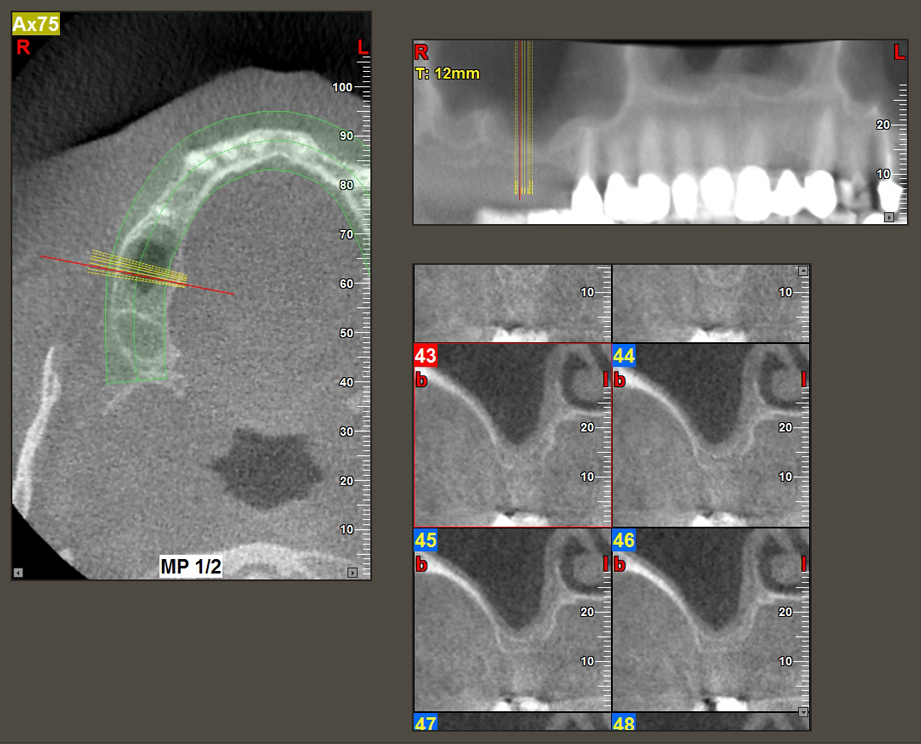

49-летняя пациентка, некурящая и не имеющая ничего примечательного в общей истории болезни, была направлена в нашу хирургическую стоматологическую клинику для хирургического удаления зуба 16 и последующей имплантации. После удаления зуба пациентка перенесла синусит в легкой форме, в результате чего мы сначала выждали шесть месяцев перед проведением операции. Остаточная высота кости при запланированном положении имплантата составляла 3-4 мм (рис. 1 и 2).

Рис.2: ДВТ имеет приемлемые размеры в каждом из аксиальных (слева), латеральных (сверху) и поперечных видов (справа).